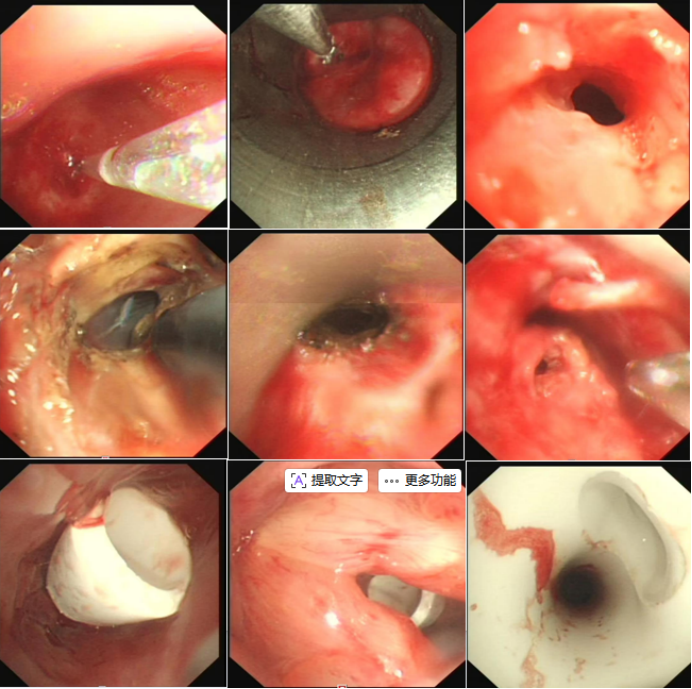

3)类型分级: 分为结构性狭窄与动力性狭窄两大类(表3)良性中心气道狭窄类型的内镜图像及示意图见图1。不同类型狭窄的病理特征与治疗策略存在显著差异。

图片

1  良性中心气道狭窄类型的内镜图像及示意图

图源:中华结核和呼吸杂志, 2017, 40(6):408-418.